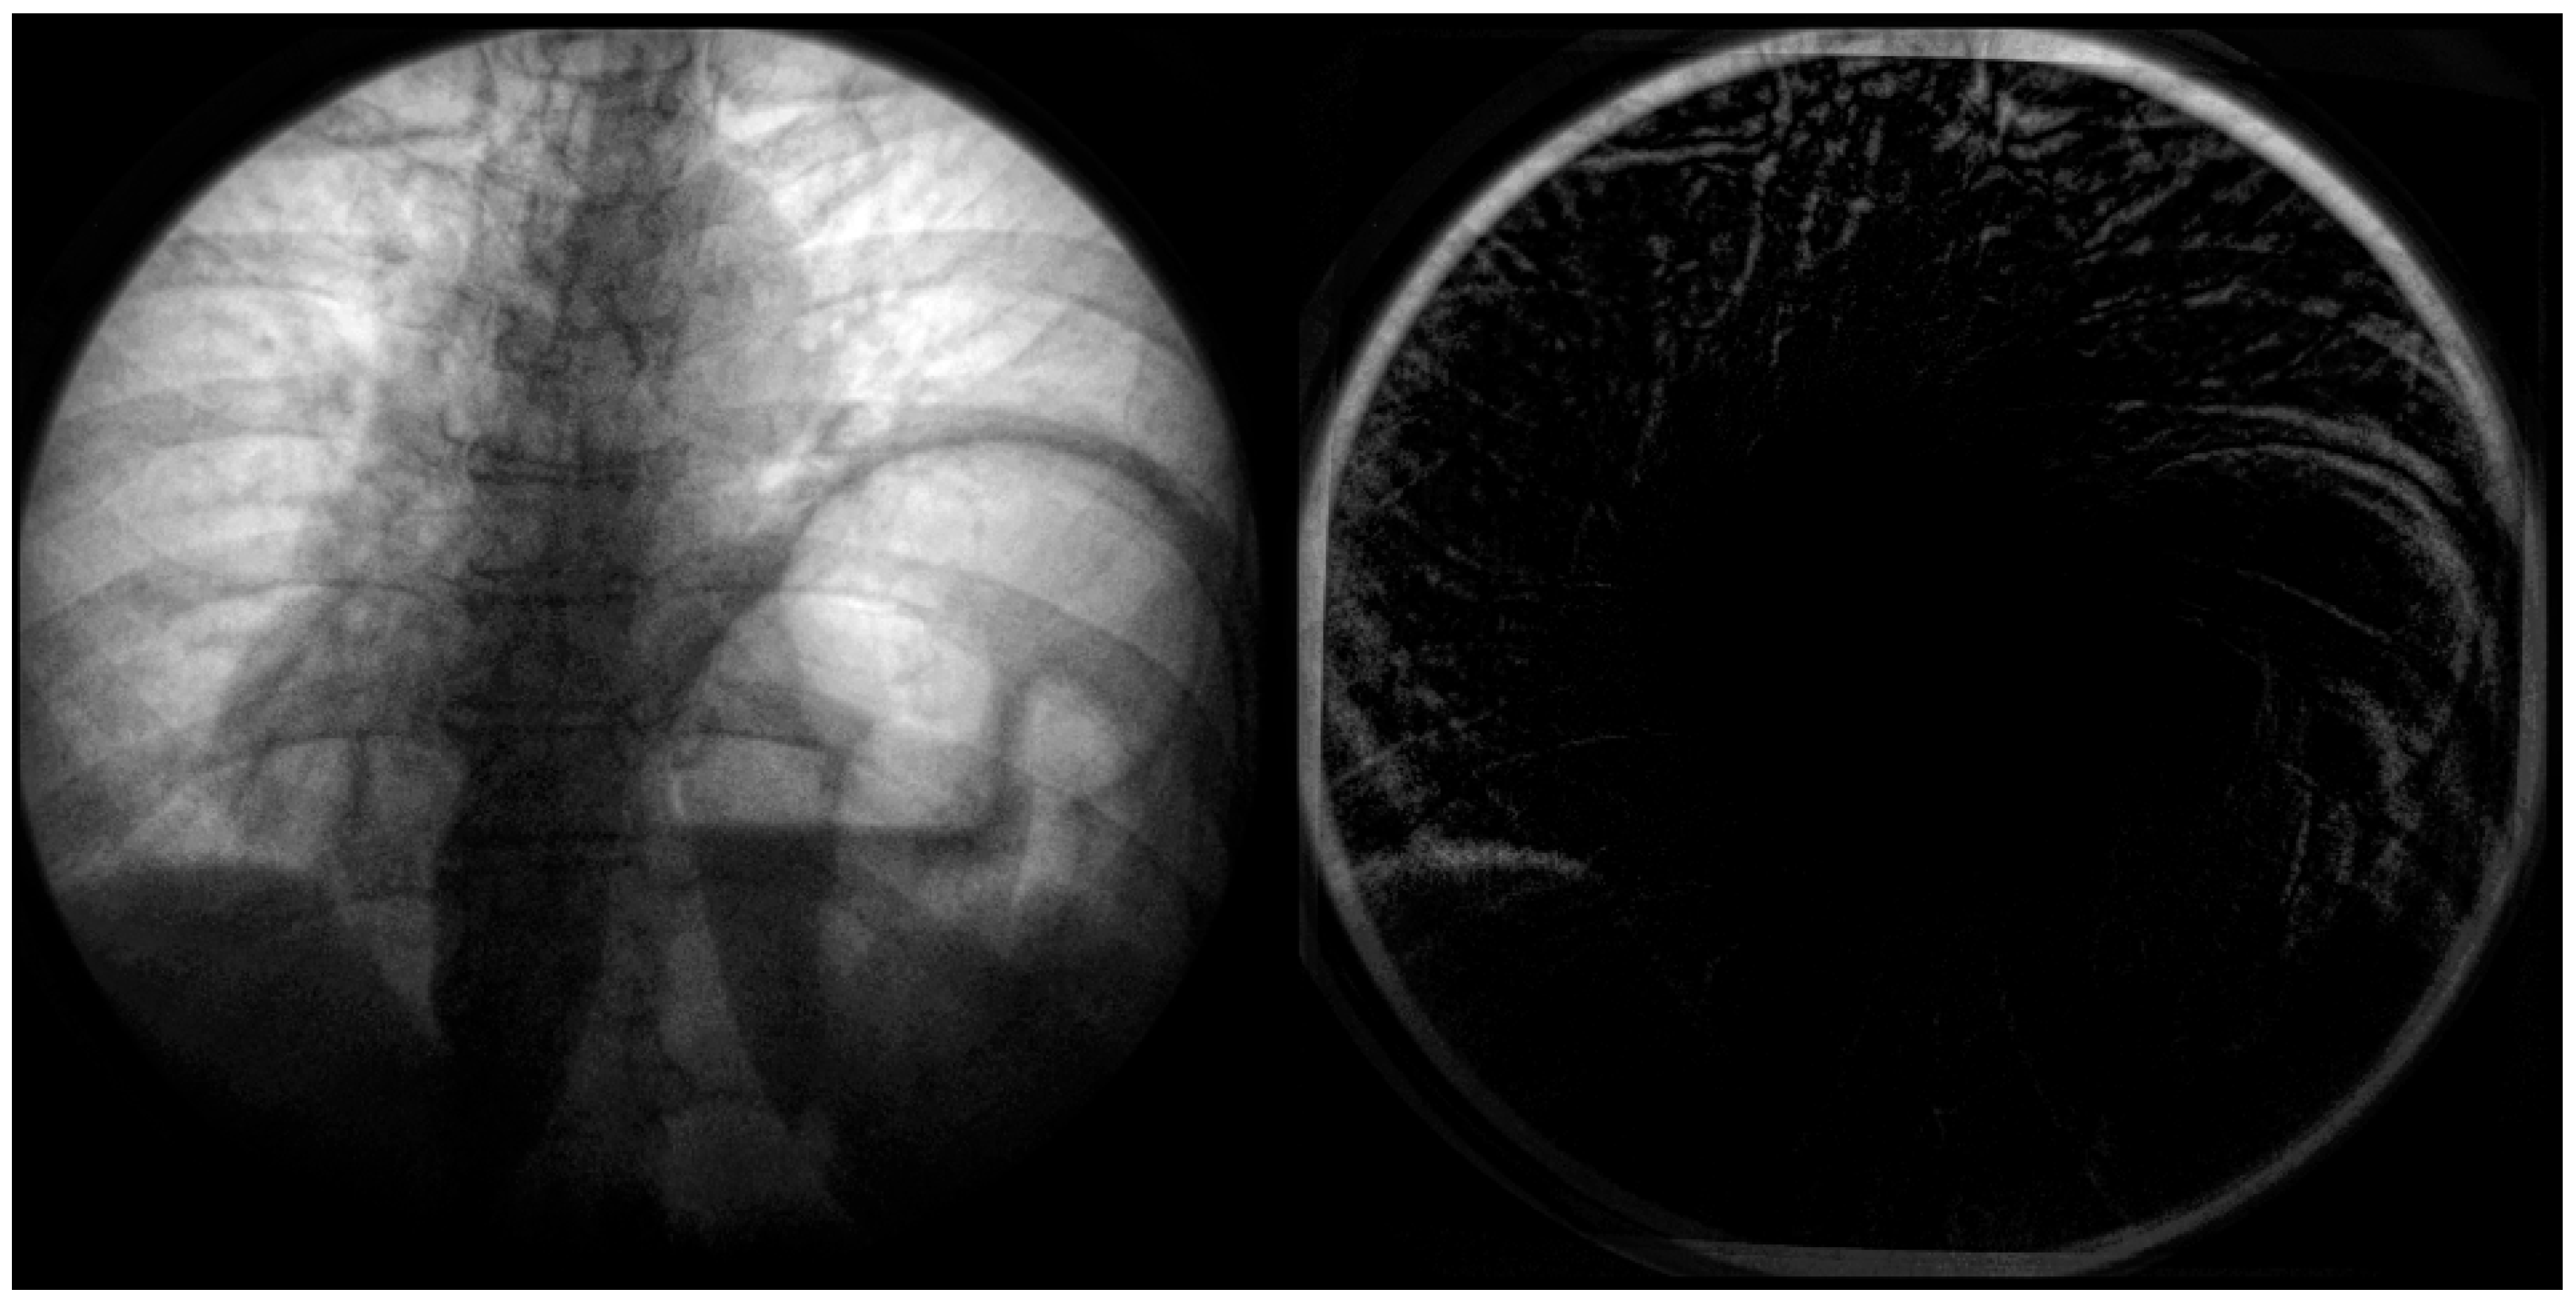

Figure 6. Imagery captured from a fluoroscopic sniff test at peak expiration from a case study of chronic left hemidiaphragm elevation [19]. A frame from the video fluoroscopy was captured pre-application of calibration (left). The geometric distortion coefficient and resulting calibration was applied to the imagery and differenced (right). Note the significant difference in the top of the diaphragm in the left of the image (right) between calibrated and non-calibrated imagery.

In the below Figure 6, the distortion is most significant radially from the center. This distortion appears primarily on anatomical features such as the ribcage, sternum, and diaphragm (Figure 7). This could significantly impact quantitative assessment if these features were used as landmarks. A side-by-side comparison can be used at the point of the diaphragm to visualize the difference between the calibrated and non-calibrated imagery.

Figure 7. Fluoroscopic spot image of the right hemidiaphragm from a fluoroscopic sniff test at peak expiration from a case study of chronic left hemidiaphragm elevation [19]. Calibrated imagery (right) and non-calibrated imagery (left) are compared. The primary shadow along the centerline represents the diaphragm’s surface. The difference in geometric position between calibrated and non-calibrated imagery can be noted.